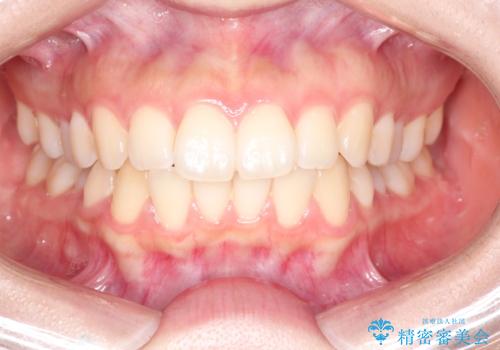

前歯のがたつきをインビザラインで目立たない矯正

- 上下の前歯のがたつきを主訴に来院されました。

マウスピースでの矯正を希望されたので、インビザラインで矯正治療を行うこととしました。

インビザラインではシュミレーションによりどのように歯が動くかを確認して矯正することができるので、患者様も安心して矯正をすることができました。